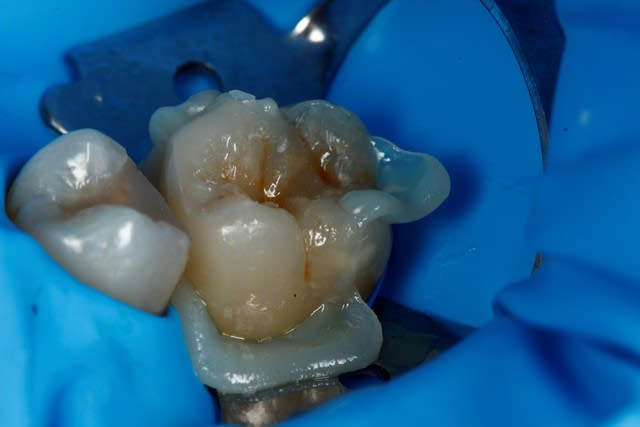

Je prends mes photos avec...un appareil photo ! :p (Canon 650D, 100mm macro, classique quoi... ;) )

Ici, je fais l'endo en essayant de garder ce que je peux de la dent...

Ensuite a la fin de l'endo, c'est propre, j'ai un accès étanche, j'en profite pour coller et remonter la limite. C'est le meilleur moment pour le faire, non ? ... Et surement le meilleur moyen d'avoir une étanchéité sur la zone faible de cette dent, sa limite proximale infra gingival.

Ensuite le cas parait plus simple bien sur Marc ;) mais en fait tout découle de la prise de décision initiale de préserver et coller...

Onlay Emax. Tout est dans l'émail a part la limite mesiale, le risque de carie est plus faible, le risque de contamination de l'endodonte plus faible aussi...

Mécaniquement ça me parait un meilleur choix que la couronne avec inlay core...